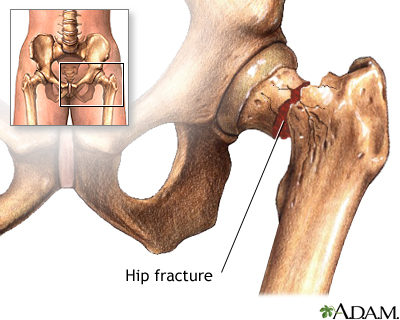

- Fractures in the thigh bone. Older adults often have a hip replacement for this reason.

Hip fracture - illustration

Hip fracture

illustration